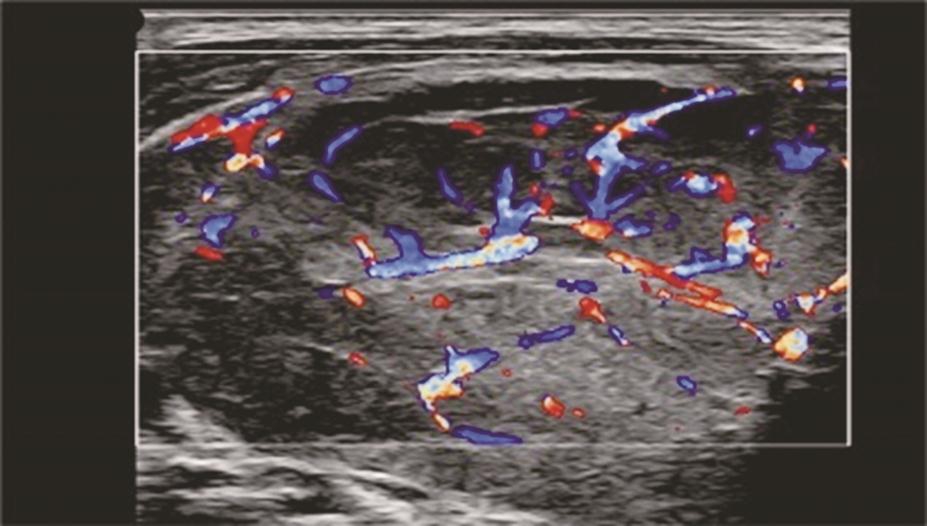

(十)甲状腺滤泡癌

甲状腺滤泡癌和滤泡腺瘤在超声上鉴别有一定困难,即使是FNA细胞学也很难鉴别。但有报道认为:与甲状腺乳头状癌不同,甲状腺滤泡癌常为等回声或高回声,微小钙化很少见,病变多伴有厚薄不一的低回声晕或者局部低回声晕。彩色多普勒血流信号丰富也是该类病变的特点之一(图11、图12)。

:中等回声彩色多普勒血流信号丰富而杂乱.jpg)

图12右侧颈部纵切面(与图3-3-11同患者、同切面):中等回声彩色多普勒血流信号丰富而杂乱